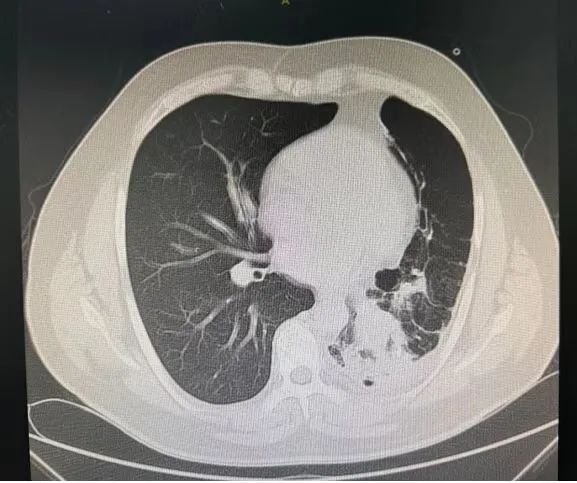

今年49岁的张先生(化名)长期饱受咳嗽、咳痰、呼吸困难的折磨,曾多次在外地医院治疗,效果不佳。近期症状加重,慕名来到哈医大一院群力院区呼吸内科于世寰教授处就诊。肺部CT检查结果令人惊讶:患者左侧气胸、左肺下叶支气管内存在可疑高密度异物阴影,并伴有阻塞性肺炎,遂急收入院。

该患者左肺下叶支气管内可疑的异物需利用呼吸内镜技术取出,但患者呼吸困难较重,肺功能很差,行支气管镜检查可能使气道压力出现变化致气胸加重,呼吸功能可能更加恶化,另外气胸患者肺组织受压后可能造成支气管镜下视野受限,因此为患者拟进行“支气管镜下异物取出术”的操作难度和风险极大。

手术当天,于世寰主任医师、李世敏副主任医师在全身麻醉保障下为患者进行手术。术中发现,患者左主支气管远端因长期异物刺激,已形成大量肉芽组织增生及瘢痕,导致管腔严重狭窄,大量脓性分泌物淤积。清除脓液后,镜下可见部分异物,但因管腔狭窄(直径小于4.2mm支气管镜),常规方法难以取出。李世敏医生谨慎运用氩气刀、电凝棒及活检钳等设备,耗时近3.5小时,逐步清除覆盖在异物周围的增生肉芽组织和瘢痕(术中需精细操作以避免出血),最终成功利用异物钳取出一枚完整的塑料笔帽。